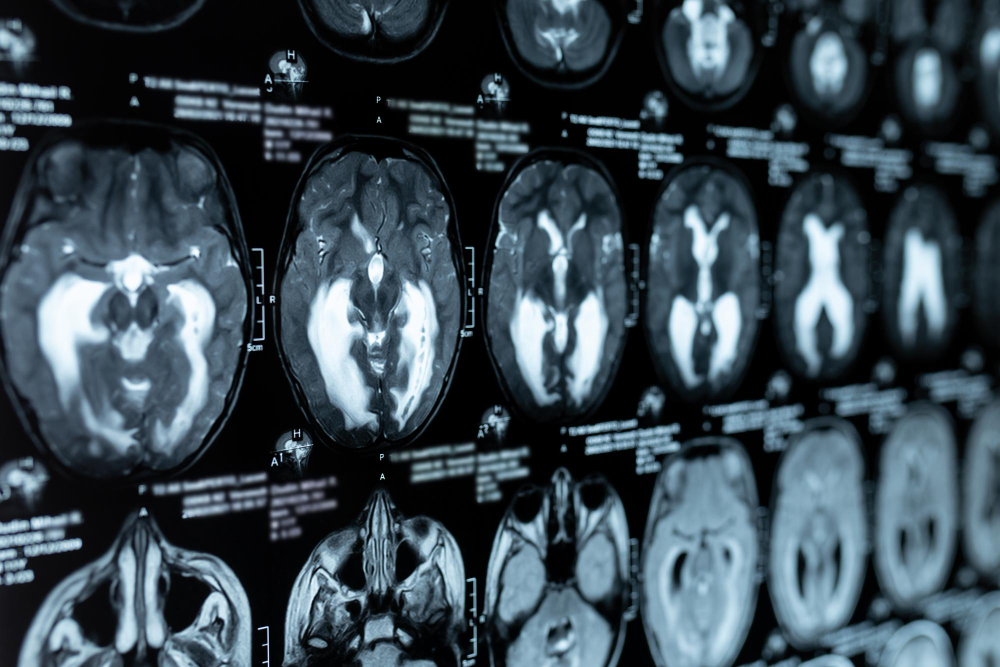

What is Hydrocephalus? Hydrocephalus is a condition where extra fluid builds up in the brain. This fluid is called cerebrospinal fluid. It protects and nourishes